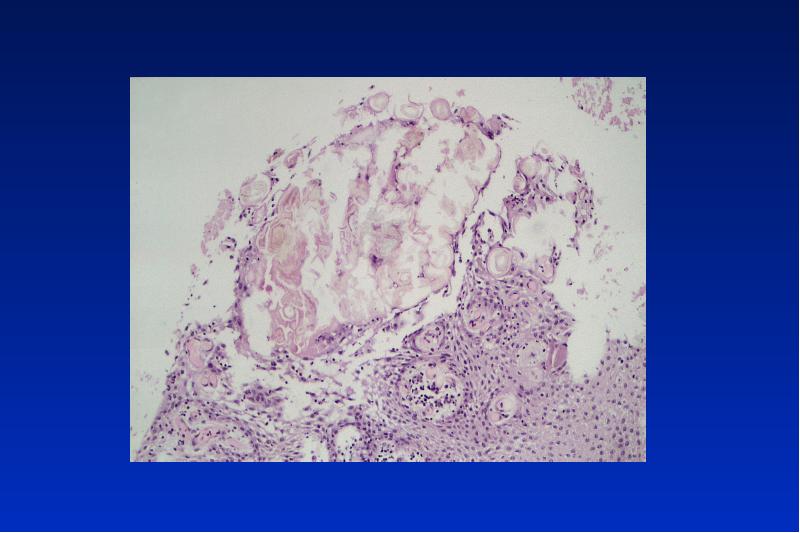

- 56. Odontom complex = gemischt compound

- 59. Kalzifizierende odontogene Zyste Odontogener Ghost cell Tumor zystisch oder solid gebaut